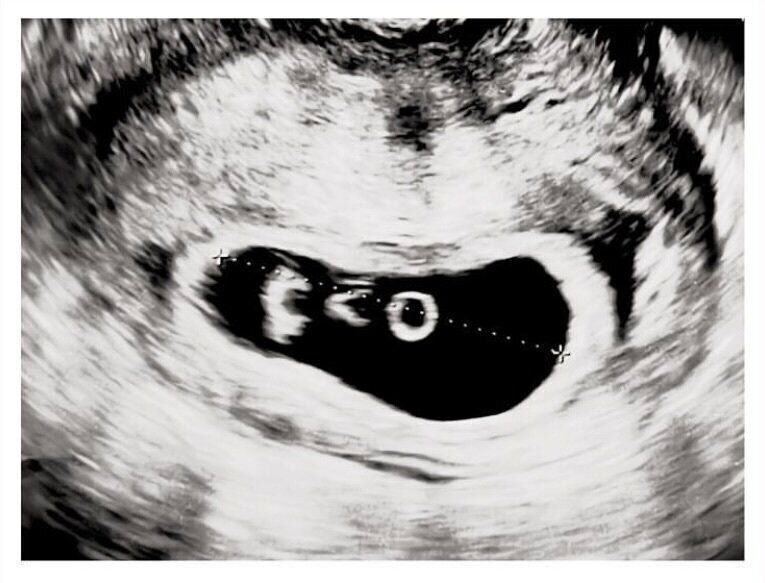

ゆき 子どもが欲しくて不妊治療をしていたときに、妊娠がわかったんです。はじめは「双子ですね」と言われて。体外受精だったのですが、戻した受精卵は1つだけ。どうやらその1つが分裂したようで、もうびっくりでした。

次の健診で先生がエコーを見ながら「1人目、2人目…」と言ったあとに、「3人目がいた」と言われたんです。

頭の中が一瞬で真っ白になりました。予想もしていない言葉でとにかく衝撃で。受精卵を1つしか戻していないのにそんなことがあるの?って。

エコーが終わり、診察室に呼ばれるまでの間、待合室でひたすらスマホ検索をしました。出てくるのは、母体や胎児のリスクや減胎手術(多胎妊娠のリスク軽減のため、一部の胎児をあらかじめ手術で減らすこと)などの情報ばかり。見れば見るほど不安が大きくなっていきました。